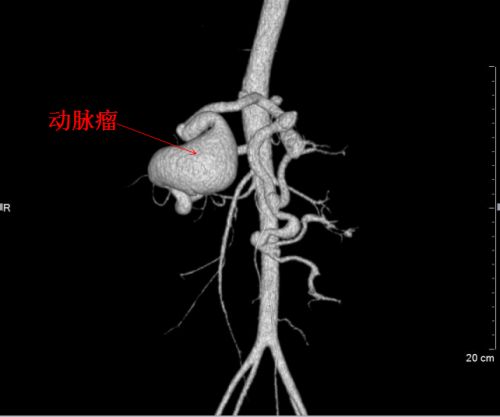

三维血管成像图看到的巨大动脉瘤。

此外,王威的脾动脉上还有一个10×6×5cm3的巨大血管瘤,占据了腹腔一半位置,将胃后壁顶起,脾动脉起始部呈螺旋状扭曲,穿行在胰腺实质中,和扩张高压的门静脉、脾静脉紧密粘连,形成可怕的“血管峡谷”。瘤体随时都可能破裂出血,就像一个“不定时炸弹”,时刻威胁着患者的生命。

反复分析三维血管成像图,制定周密的手术方案后,5月21日,王俊教授、吕品主任医师等组成“拆弹部队”,在麻醉科、手术室的密切配合下,打开患者的腹腔。令人胆战心惊的一幕呈现在医护人员眼前——在高动力血流的冲击下,巨大的动脉瘤瘤体薄如蛋壳,并且随着心脏的搏动而颤动,似乎轻微的扰动就会让血流冲破“壳体”汹涌而出。关键是,瘤体一旦破裂,医生根本无法在脆弱的血管表面进行缝合止血,那将导致灾难性的后果!